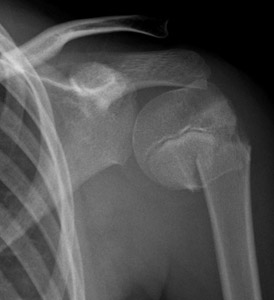

Figure-1_1333311_Proximal_humerus_AP.jpg  Figure-1_1333311_Proximal_humerus_Lat.jpg

Figure 1AP and lateral x-ray of 10 year old girl with Salter-Harris type II fracture of the proximal humerus.